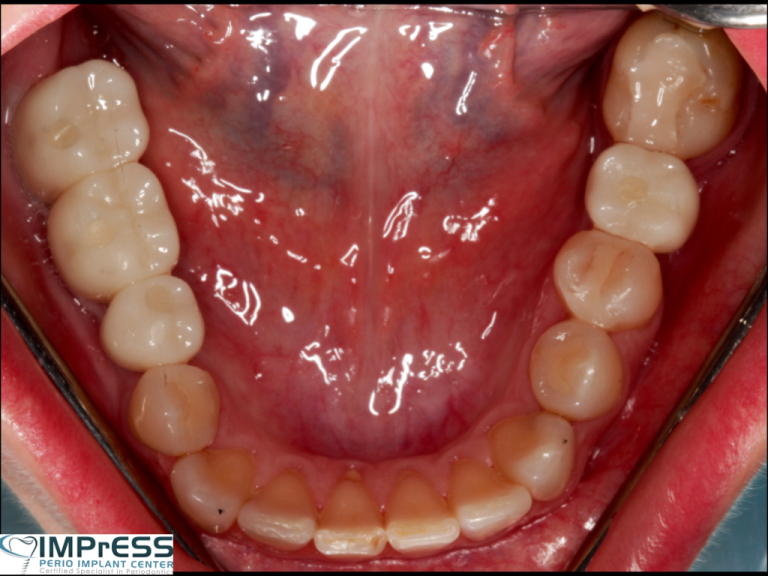

Bone Grafting for implants Guided Implant Surgery Implant Bridge Dr. Noroozi Vancouver Implant Specialist IMPrESS Perio Implant Center